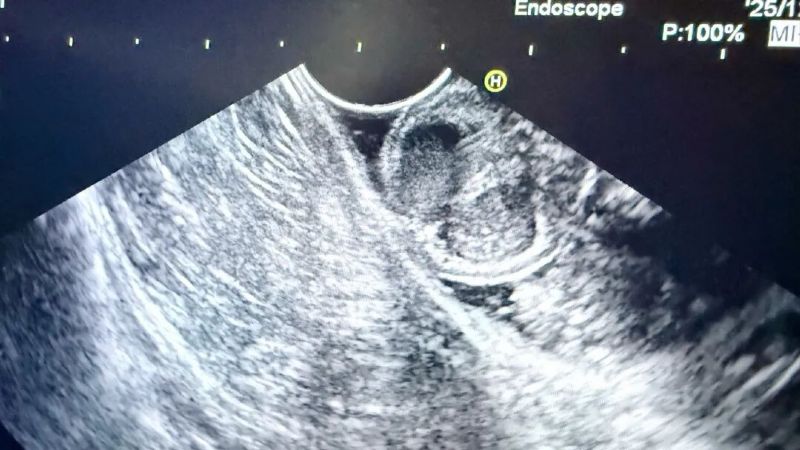

为进一步明确病变性质与起源层次,消化内科二病区张荣主任团队为患者安排了增强CT、超声内镜等一系列精密检查。完善上述检查后,结合影像学特征考虑良性病变可能性大,但仍无法完全排除恶性可能,病变性质的最终判定,必须依靠完整切除标本后的病理诊断。

患者超声内镜以及胃镜图